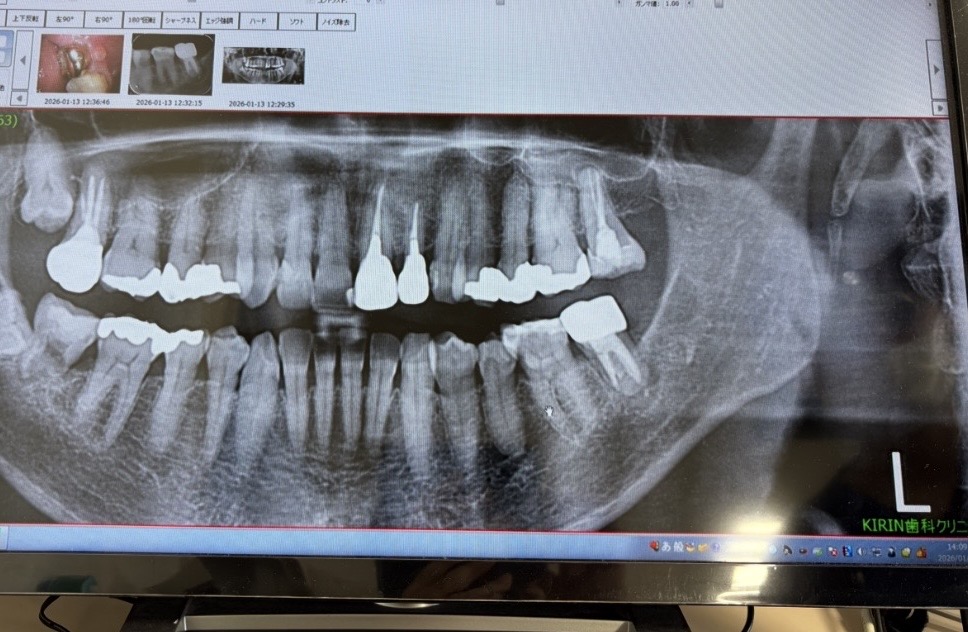

歯の根の下に黒っぽい場所(黄緑でマーキング親知らず側)があってそこから歯茎の方に膿が出ている。

CT画像からはハッキリ破折を認められない。

少し線が見える場所が6番の歯側にあるが、黄緑でマーキングした場所は根幹治療で薬が入っているところと根の治療の境目で破折ではない可能性もある とのこと。

奥歯7番は根幹治療をしてもなかなか難しい場所で、根の形がCTで見ると、Cという文字のようなかたちでつながっていると、余計難しいとのことでした。